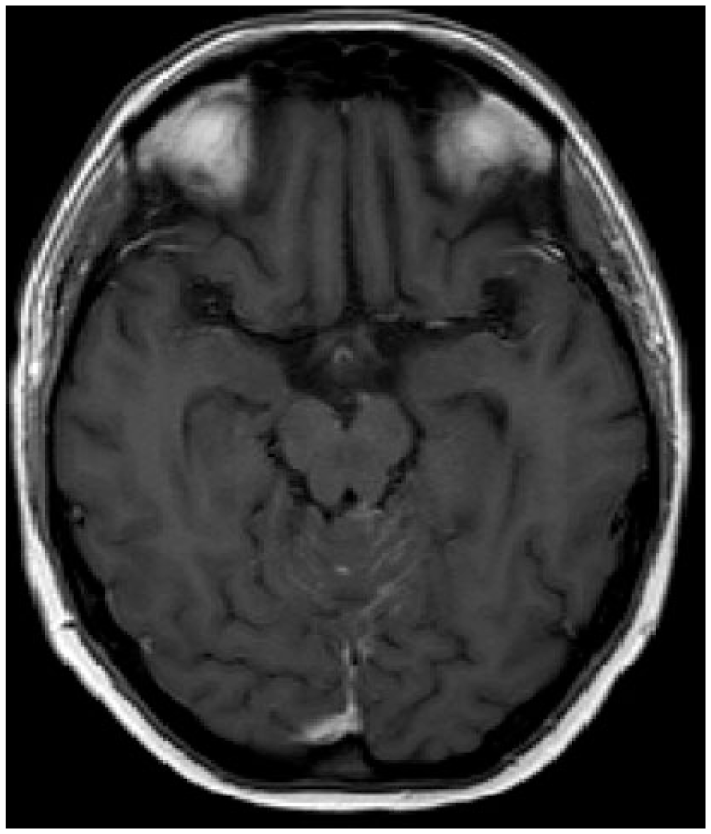

Linear or nodular enhancing lesions of the cranial nerves and spinal nerve roots (e.g. cauda equine), brain sulci and cerebellar foliae are the most common findings32,33 (Figures 1–3). NM lesions typically are small in size (<5 mm) and with complex geometry, thus a quantitative analysis with current MRI technology is difficult. 34 Other neuroimaging techniques (MRI spectroscopy, MRI perfusion, MRI diffusion and positron emission tomography) are not currently employed. Communicating hydrocephalus could be observed in 11–17% of patients, and CSF flow studies, including radioisotope cisternography, are useful in the case of suspected CSF blockage or altered intrathecal drug delivery.35,36

Linear enhanced lesions in cerebellar foliae.